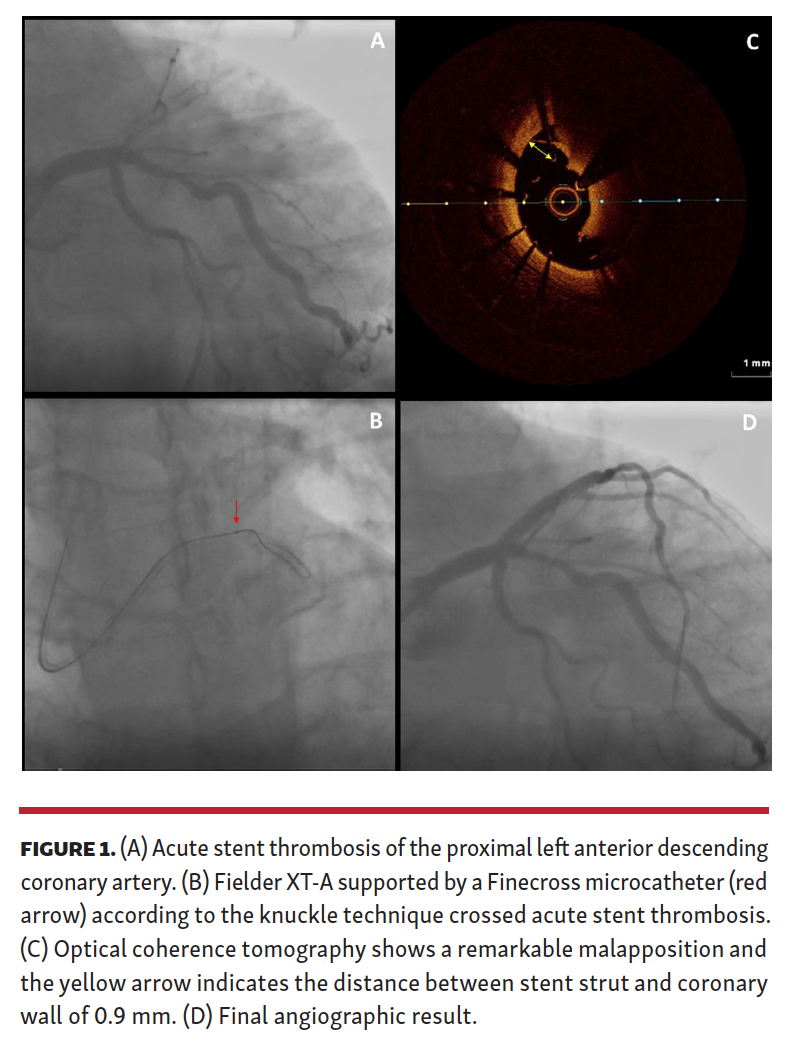

A 65-year-old man underwent primary angioplasty and stent implantation on the proximal left anterior descending (LAD) coronary artery. Morphine 10 mg, heparin, and ticagrelor loading dose were administered during the procedure. However, 6 hours post procedure, the patient experienced cardiac arrest due to ventricular fibrillation. We repeated an urgent coronary angiography (Figure 1A), which showed an acute stent thrombosis (ST). Since the P2Y12 reactivity unit (PRU) value was 212 (corresponding to 12% platelet inhibition) as assessed by VerifyNow assay (Accumetrix) after cardiac arrest, we administered tirofiban. We were not able to overcome the acute ST of the LAD with workhorse wires, and instead performed a rapid step-up to a Fielder XT-A (Asahi Intecc) supported by a FineCross microcatheter (Terumo). We quickly gained the distal LAD (Figure 1B and Video 1). After manual thrombectomy, we performed optical coherence tomography (OCT), which revealed a severe in-stent malapposition (Figure 1C). After additional manual thrombectomy, 1 drug-eluting stent was implanted at the proximal edge of the previous stent to cover the residual disease. The final angiographic result was good (Figure 1D).

Acute ST is a rare event, but procedure- and patient-related factors need to be assessed. First, only with a chronic total occlusion derived technique, wiring was successful demonstrating indirectly a stent-related problem. OCT showed a remarkable in-stent malapposition. Another important factor that contributed to acute ST was the insufficient platelet inhibition because morphine negatively affected ticagrelor absorption and onset of action. When acute ST occurs, multiple partners in crime should be investigated.